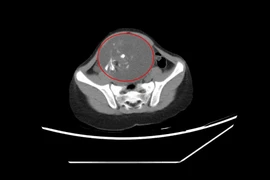

Đau bụng vùng hố chậu phải, kèm theo nôn ói, bệnh nhi được gia đình cho uống thuốc nhưng không cải thiện, đi khám phát hiện khối u buồng trứng trái bị xoắn hiếm gặp.

U buồng trứng xoắn thường xuất hiện ở độ tuổi 20–30, rất hiếm gặp ở trẻ em. Triệu chứng của bệnh thường âm thầm, dễ nhầm lẫn với các bệnh lý khác và có thể gây ảnh hưởng lớn đến khả năng sinh sản sau này của trẻ gái.

Xoắn buồng trứng hay xoắn tai vòi là một cấp cứu ngoại khoa thường gặp ở bé gái. Tại Bệnh viện Nhi đồng 2, mỗi năm tiếp nhận khoảng hơn 100 ca phẫu thuật cấp cứu liên quan đến xoắn buồng trứng... cha mẹ cần biết cách phát hiện sớm.